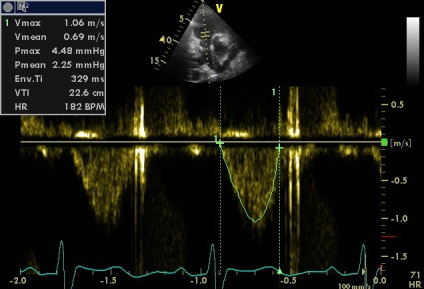

az aortabillentyű áramlási

2. fokozott gradiens aortabillentyű (18.57) és megközelítőleg azonos VTI LVOT VTI Ao és úgy kell értelmezni, egyszerűen következtében tachycardia?

2. megnövekedett gradiens aortabillentyű (18.57) és megközelítőleg azonos VTILVOTi VTIAosleduet értelmezni egyszerűen következtében tachycardia?

Tachycardia idején szkennelés nem (a klip jobb alsó sarkában a csatorna EKG monitorozás szívritmus alakzatnak, akkor változik a 73-77 perc). De érszűkület (akár minimális) szintén nem (igazad van), és enyhe növekedés sebessége és a színátmenet összefüggésbe hozható a megnövekedett perctérfogat (verőtérfogat LV). „Körülbelül egyenlő a VTI” csak beszélni a közelítő egyenlőség a terület és a terület AK BT LV (aorta regurgitatio nem számít, mert még kicsi, annak ellenére, hogy az alacsony PHT. Ebben az esetben a gyorsított összehangolás LZH- Ao nyomás nem jár gyors növekedése a diasztolés nyomás a bal kamrában, mint a súlyos aorta regurgitáció, és a gyors nyomás csökkenése az aortában miatt ürítőnyílás a sipoly).